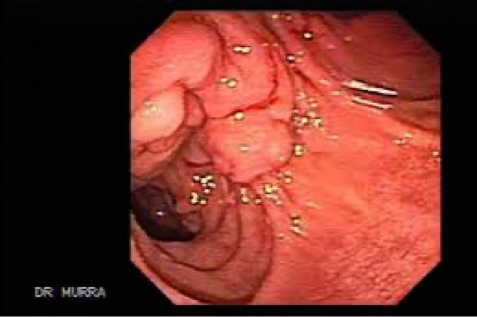

Periampullary tumor (endoscopic view)

Tumor in the head of pancreas: painless obstructive jaundice associated with weight loss is the classical presentation due to obstruction of the CBD. Obstruction of the flow of bile to the intestine will disrupt the enterohepatic circulation which results in dark urine and pale stool. The patient may also have intense itching. The gallbladder may become dilated and palpable (Courvoisier’s sign or law).